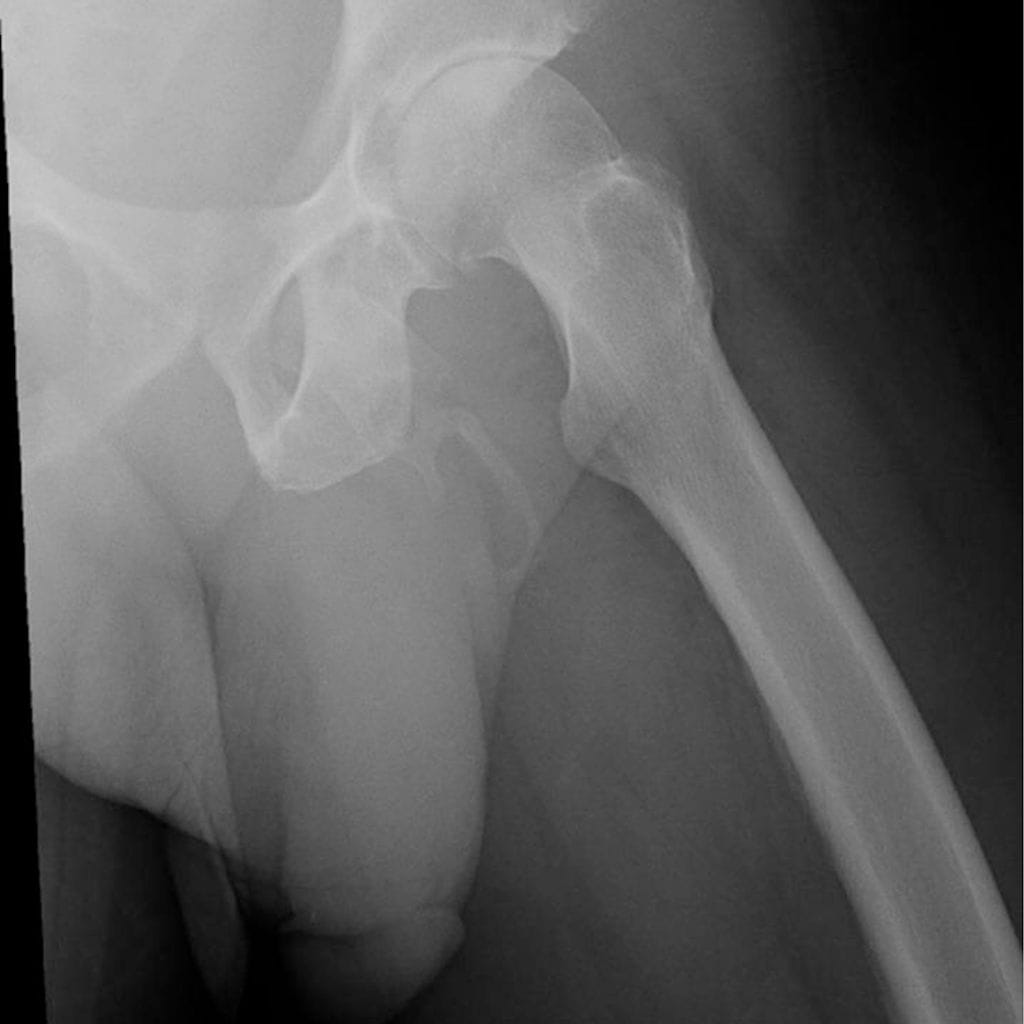

Miehen peniksessä havaittiin plakkimaista kalkkeutumista. Lääkärit huomasivat siittimen alkaneen luutua koko vartensa mitalta, Urology Case Reports -julkaisussa ilmestyneessä tapausraportissa kerrotaan.

Peniksen luutumisen uskotaan olevan seurausta kalsiumsuolojen kertymisestä peniksen paisuvaiskudokseen, kertoo tapauksesta uutisoinut Gizmodo-sivusto.

Perinteisesti peniksen luutuminen on yhdistetty Peyronin tautiin, jota arvioidaan esiintyvän noin yhdellä prosentilla miehistä. Peyronin taudissa peniksen paisuvaiskalvo paksuuntuu ja siihen muodostuu sidekudoksen kovettumaa, kertoo Terveyskylä-sivusto. Tauti voi aiheuttaa erektiokipua, peniksen käyristymistä, kaventumista ja lyhenemistä.